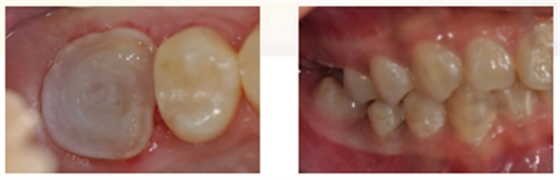

复诊,无不适,去除冠部暂封,试主牙胶尖,拍摄X-ray。

iROOT SP糊剂单尖法根充四根管,SDR树脂髓腔充填,拍摄X-ray,显示根管充填完好。

牙体预备制取26高嵌体工作模型

复诊,无不适,上橡皮障,粘接树脂高嵌体

三个月复查